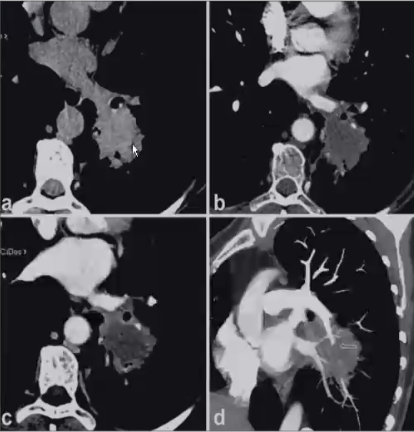

❖ CT增强(强化程度,低密度征)

❖ CTPA:结节或肿块样病变内血管改变